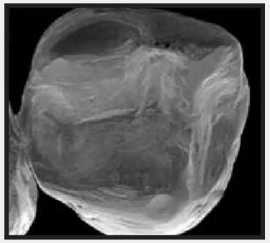

復合樹脂在即刻充填后,觀察其在電子顯微鏡下的掃描圖像,本次研究選擇了9種具有代表性的復合樹脂材料。

1.png

Clearfil Majesty Kuraray America 可樂麗